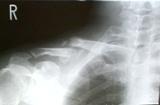

転倒して一週間目の受診でした.本当は,今日で治療終了・完治のはずでしたが,最初の骨折から85日,再度の骨折で7日目になりました.85日(7日).

受診前のレントゲン写真を見て担当医から;

�なぜ,当日来なかったのですか?

�今度は,上下に離れているのでくっ付かないかもしれない.その場合は,手術になる

�もう直ぐ治癒だったのに,また始めからです.

�珍しいです.同じ鎖骨を三回も骨折するとは(一回目は,バイク事故で)

手術は,骨折部に別の所(腸骨)から移植をして,プレート固定,入院期間は7〜10日間とのことでした.